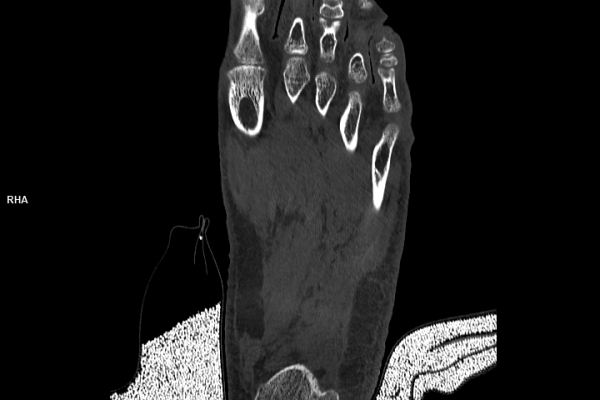

CT Untersuchung Bild

Detailbild MRT